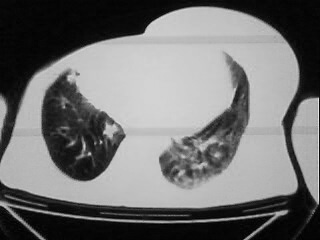

以下是引用随光逐影在2009-2-10 0:07:00的发言:[br]1)右肺放射性肺炎并节段性肺不张?请结合相关病史。2)右侧胸膜肥厚、粘连。3)心包膜增厚(或心包少量积液)。